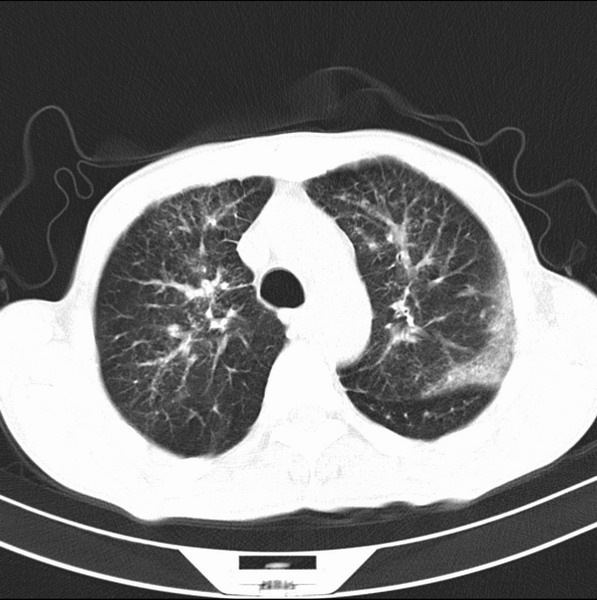

未发现确切,暂时考虑炎症,建议抗炎治疗后复查

考虑间质性病变,癌性淋巴管炎可能.

转移,癌性淋巴管炎。

建议抗炎后复查,不除外癌性淋巴管炎。

炎性并间质纤维化

炎性并间质纤维化,请询问病史,如用过平阳霉素或其他化疗药.可能为药物引起的间质纤维化.